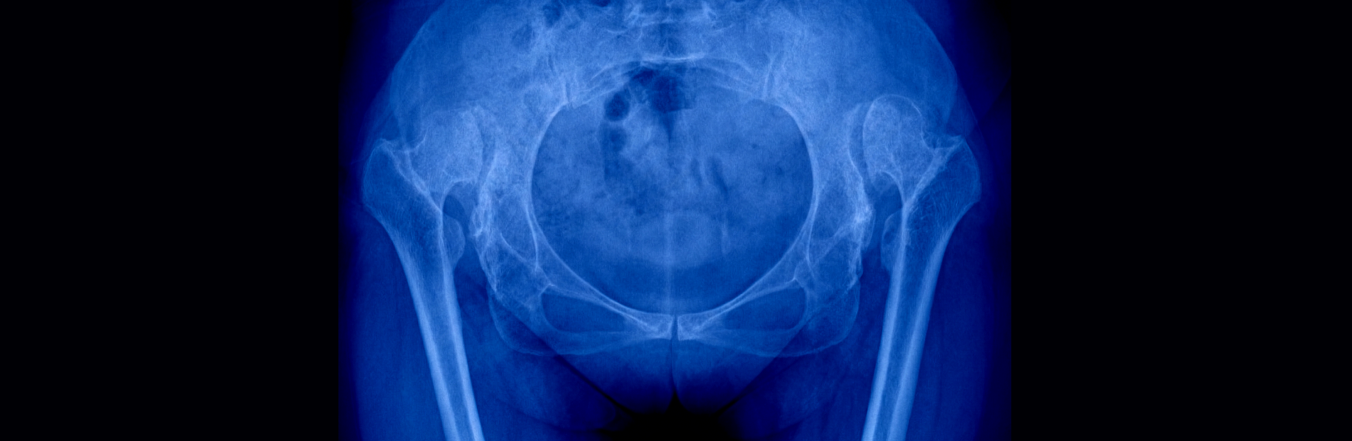

Cos'è la displasia dell'anca

La displasia dell’anca è una condizione in cui la testa del femore non si inserisce correttamente nella cavità acetabolare del bacino, determinando un’articolazione instabile e predisposta a lussazioni o usura precoce.

Diagnosi e percorso di valutazione per la displasia dell'anca

La diagnosi si basa su un esame clinico approfondito e l’utilizzo di esami strumentali adeguati all’età e alla complessità del quadro clinico.

Nei neonati si privilegia l’ecografia articolare, mentre negli adolescenti e adulti si eseguono radiografie mirate, risonanza magnetica e TAC per valutare la conformazione e lo stato dei tessuti.